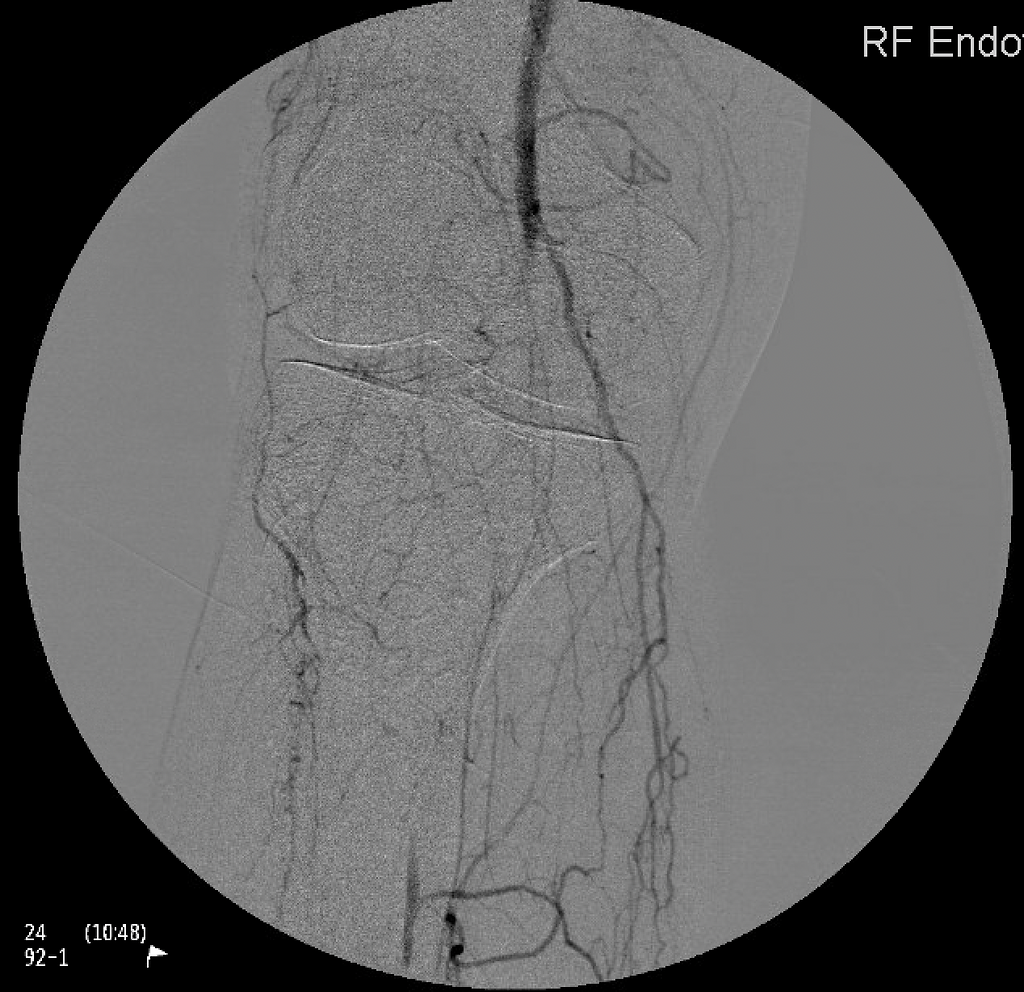

Endovascular treatment for arterial disease utilizes minimally invasive procedures, like angioplasty and stent placement, to restore and support blood flow, providing effective and targeted interventions for improved vascular health.